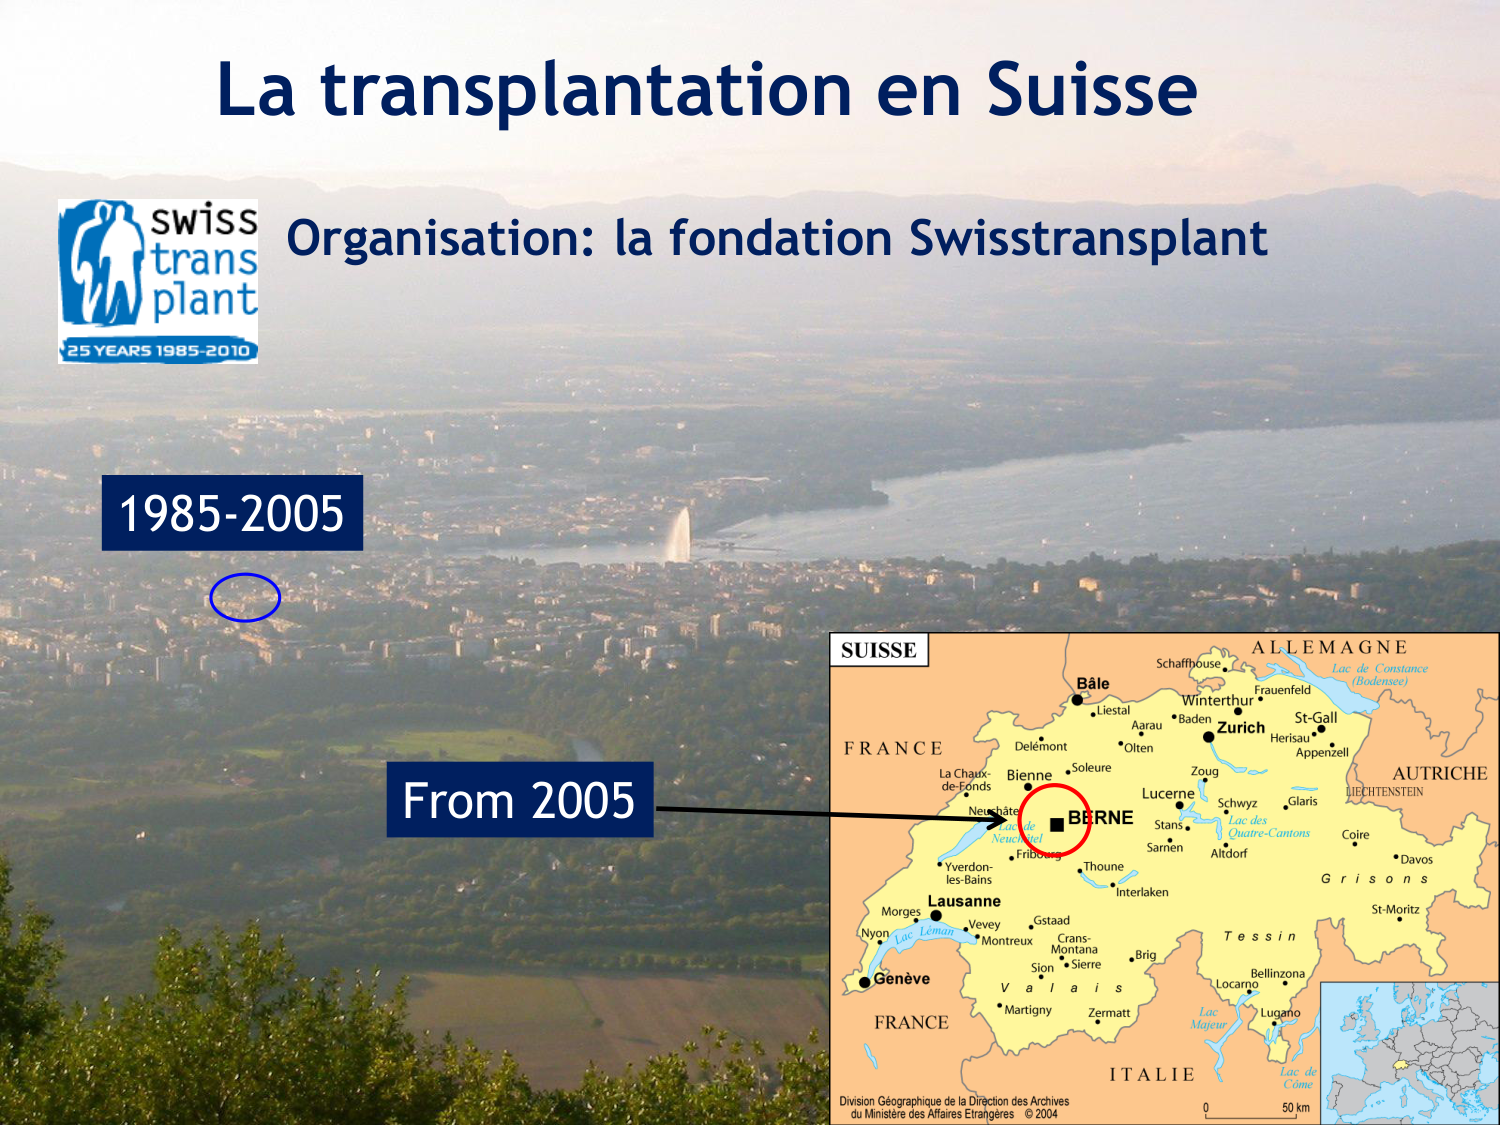

SMB4 Systèmes physiologiques 2 Immunologie, inflammation, transplantation · 61 pages · 8 sections